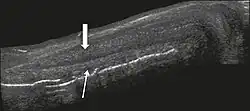

Venous drainage is performed by the deep and superficial dorsal veins of the penis. The dorsal arteries of the penis are located adjacent to the deep dorsal vein and a cavernous artery is located in the center of each corpus cavernosum. On color Doppler, the cavernous arteries present single phase flow. In the flaccid penis (Figure 3), the normal cavernous arteries show a systolic peak between 11 and 20 cm/s. At the beginning of erection, the systolic and diastolic flows undergo progressive increases. When vein occlusion begins, the diastolic flow decreases progressively, and once stiffness is established, it becomes negative.[1]